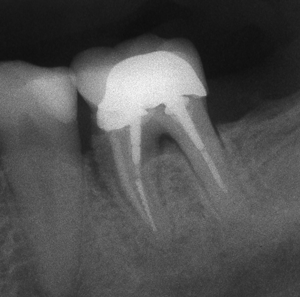

Фрактура на корена

Фрактуриран зъбен корен